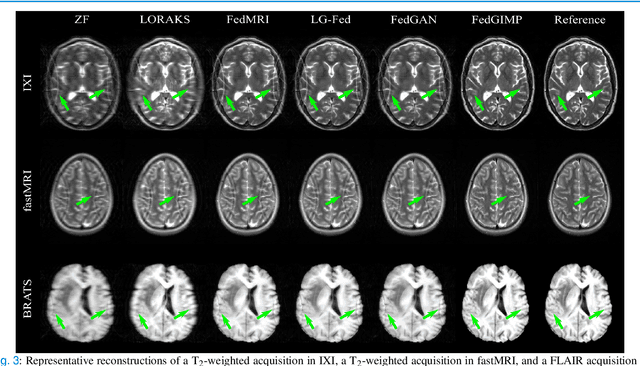

Abstract:Multi-institutional efforts can facilitate training of deep MRI reconstruction models, albeit privacy risks arise during cross-site sharing of imaging data. Federated learning (FL) has recently been introduced to address privacy concerns by enabling distributed training without transfer of imaging data. Existing FL methods for MRI reconstruction employ conditional models to map from undersampled to fully-sampled acquisitions via explicit knowledge of the imaging operator. Since conditional models generalize poorly across different acceleration rates or sampling densities, imaging operators must be fixed between training and testing, and they are typically matched across sites. To improve generalization and flexibility in multi-institutional collaborations, here we introduce a novel method for MRI reconstruction based on Federated learning of Generative IMage Priors (FedGIMP). FedGIMP leverages a two-stage approach: cross-site learning of a generative MRI prior, and subject-specific injection of the imaging operator. The global MRI prior is learned via an unconditional adversarial model that synthesizes high-quality MR images based on latent variables. Specificity in the prior is preserved via a mapper subnetwork that produces site-specific latents. During inference, the prior is combined with subject-specific imaging operators to enable reconstruction, and further adapted to individual test samples by minimizing data-consistency loss. Comprehensive experiments on multi-institutional datasets clearly demonstrate enhanced generalization performance of FedGIMP against site-specific and federated methods based on conditional models, as well as traditional reconstruction methods.